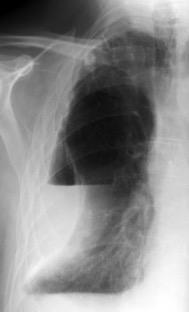

Fallece en el acto de tomar esta radiografía. La mayoría ateroescleróticos. Más frecuente a la derecha.La rotura: 32-47% de las muertes.